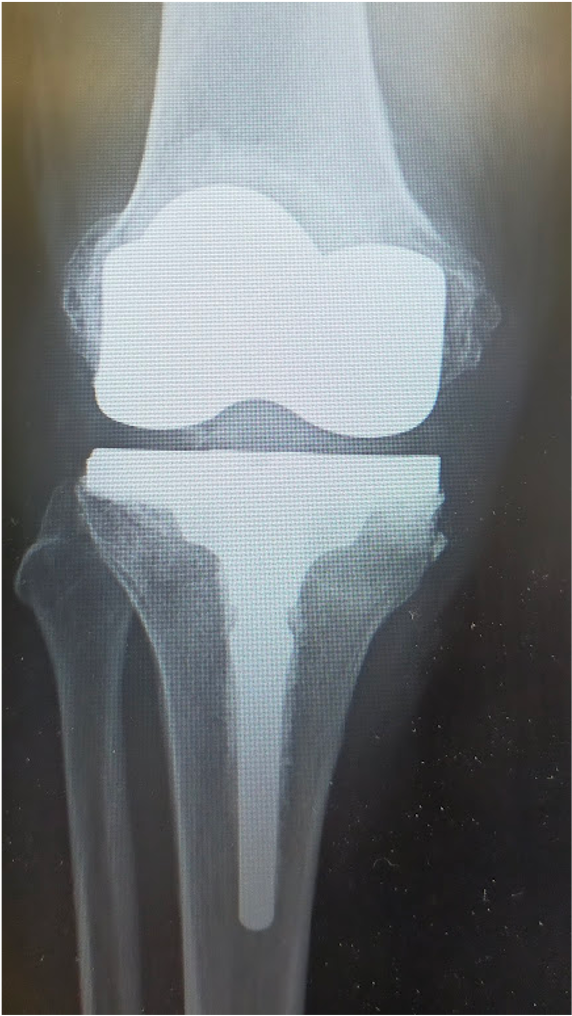

傷んだ関節表面を人工関節の形に合わせて削り、金属、セラミック、ポリエチレンでできた人工関節を骨の上に固定します。この手術を受けることで、関節の動きが滑らかになり、O脚やX脚といった変形が改善し、まっすぐな脚にすることが出来ます。人工関節の耐久性は10年間弛みなく日常生活が送れる可能性が95%以上といわれ、長期的にも安定した方法です。さらに最新の人工関節では性能が格段に良くなっており、20〜30年以上の機能することも十分期待できるようになってきました。

当院にて右人工膝関節全置換術(TKA)を施行。術前、歩行も困難でしたが、術後は杖歩行も安定し、良好な可動域も獲得。入院中に反対側の人工膝関節単顆置換術(UKA)も行い、十分なリハビリ後に退院となりました。

[手術後]

〈手術後〉(右ひざ)

〈手術後のレントゲン〉

右TKA後

〈手術後のレントゲン〉(正面・側面)

右膝